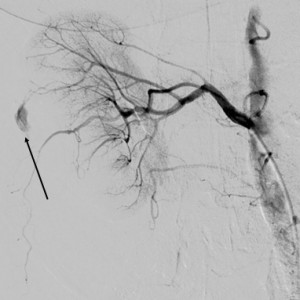

The patient was under observation on the cathlab floor during the next 60 minutes and after that the sheath was removed and hemostasis was achieved. She returned to her room but no longer then 15 minutes after she reported nausea, diaphoresis and weakness. Hypoglycemia was initially suspected but the glucotest showed a 260 mg/dl value of the serum glucose. The patient became hypotensive (systolic blood pressure 80 mm Hg) and soon after she complained of increasing pain in the right lumbar area. An ultrasound made at the bedside showed a right perirenal hematoma. The lab test indicated a dramatic decrease in the hemoglobin level, from 13 mg/dl to 8.0 mg /dl. The patient was practically in hemorrhagic shock. The decision was to transfer immediately the patient to the cathlab for an angiographic control. A new puncture of the right femoral artery was made, because the initial suspicion was an iliac rupture or perforation in the stent area, due to the extensive calcification of the arterial wall. The first injection of contrast media through the sheath showed that there was no problem with the stent. After that a global injection into the abdominal aorta, at the renal arteries level, was made, and a small effraction in the right renal parenchyma was observed (Figure 3). Selective intubation of the right renal artery was made with a JR 4.0 diagnostic catheter and that confirmed the source of bleeding in the right posterior segmental artery (Figure 4). Careful superselective intubation of this branch was performed (Figure 5), and small particles of gelatin sponge (Gelaspon) mixed with contrast media were delivered through the catheter. The embolization7 was successful in stopping the bleeding (Figure 6) but since there was about 20% of the renal parenchyma without vascularization and the patient still had important pain in the lumbar area, the decision was to transfer her to the urology department. A CT-scan (Figure 7) indicated a large subcapsular and retroperitoneal hematoma and also the presence of the contrast media in the urinary tract, an indication that the renal function was still preserved. In accordance with these findings, a renal lobectomy (partial nephrectomy) was performed, along with the evacuation of the hematoma. There was a parenchymal sparing intervention that preserved almost the entire kidney. The outcome was complicated by a pneumothorax after a central venous catheter insertion and by a right femoral hematoma following the two arterial punctures. However, after 14 days the patient was discharged in pretty good condition. One year later she has no claudication, the pulse in the right femoral artery is very good and the serum creatinine is normal.

Figure 4. Selective injection in the right renal artery; arrow indicates the site of the effraction.